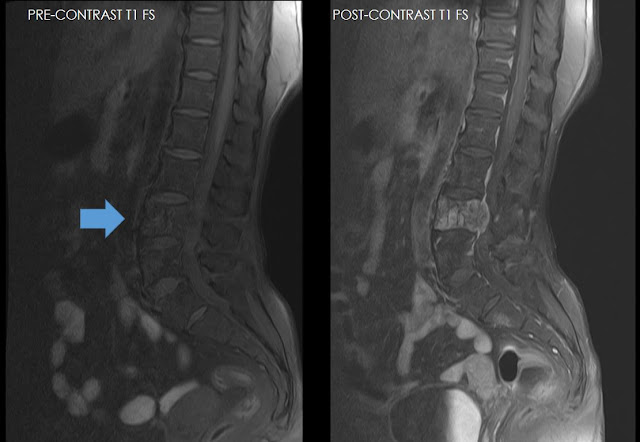

Ultimate Radiology : Aggressive ('Malignant') Hemangioma Of Vertebrae

hemangioma aggressive contrast enhancement intense radiology malignant